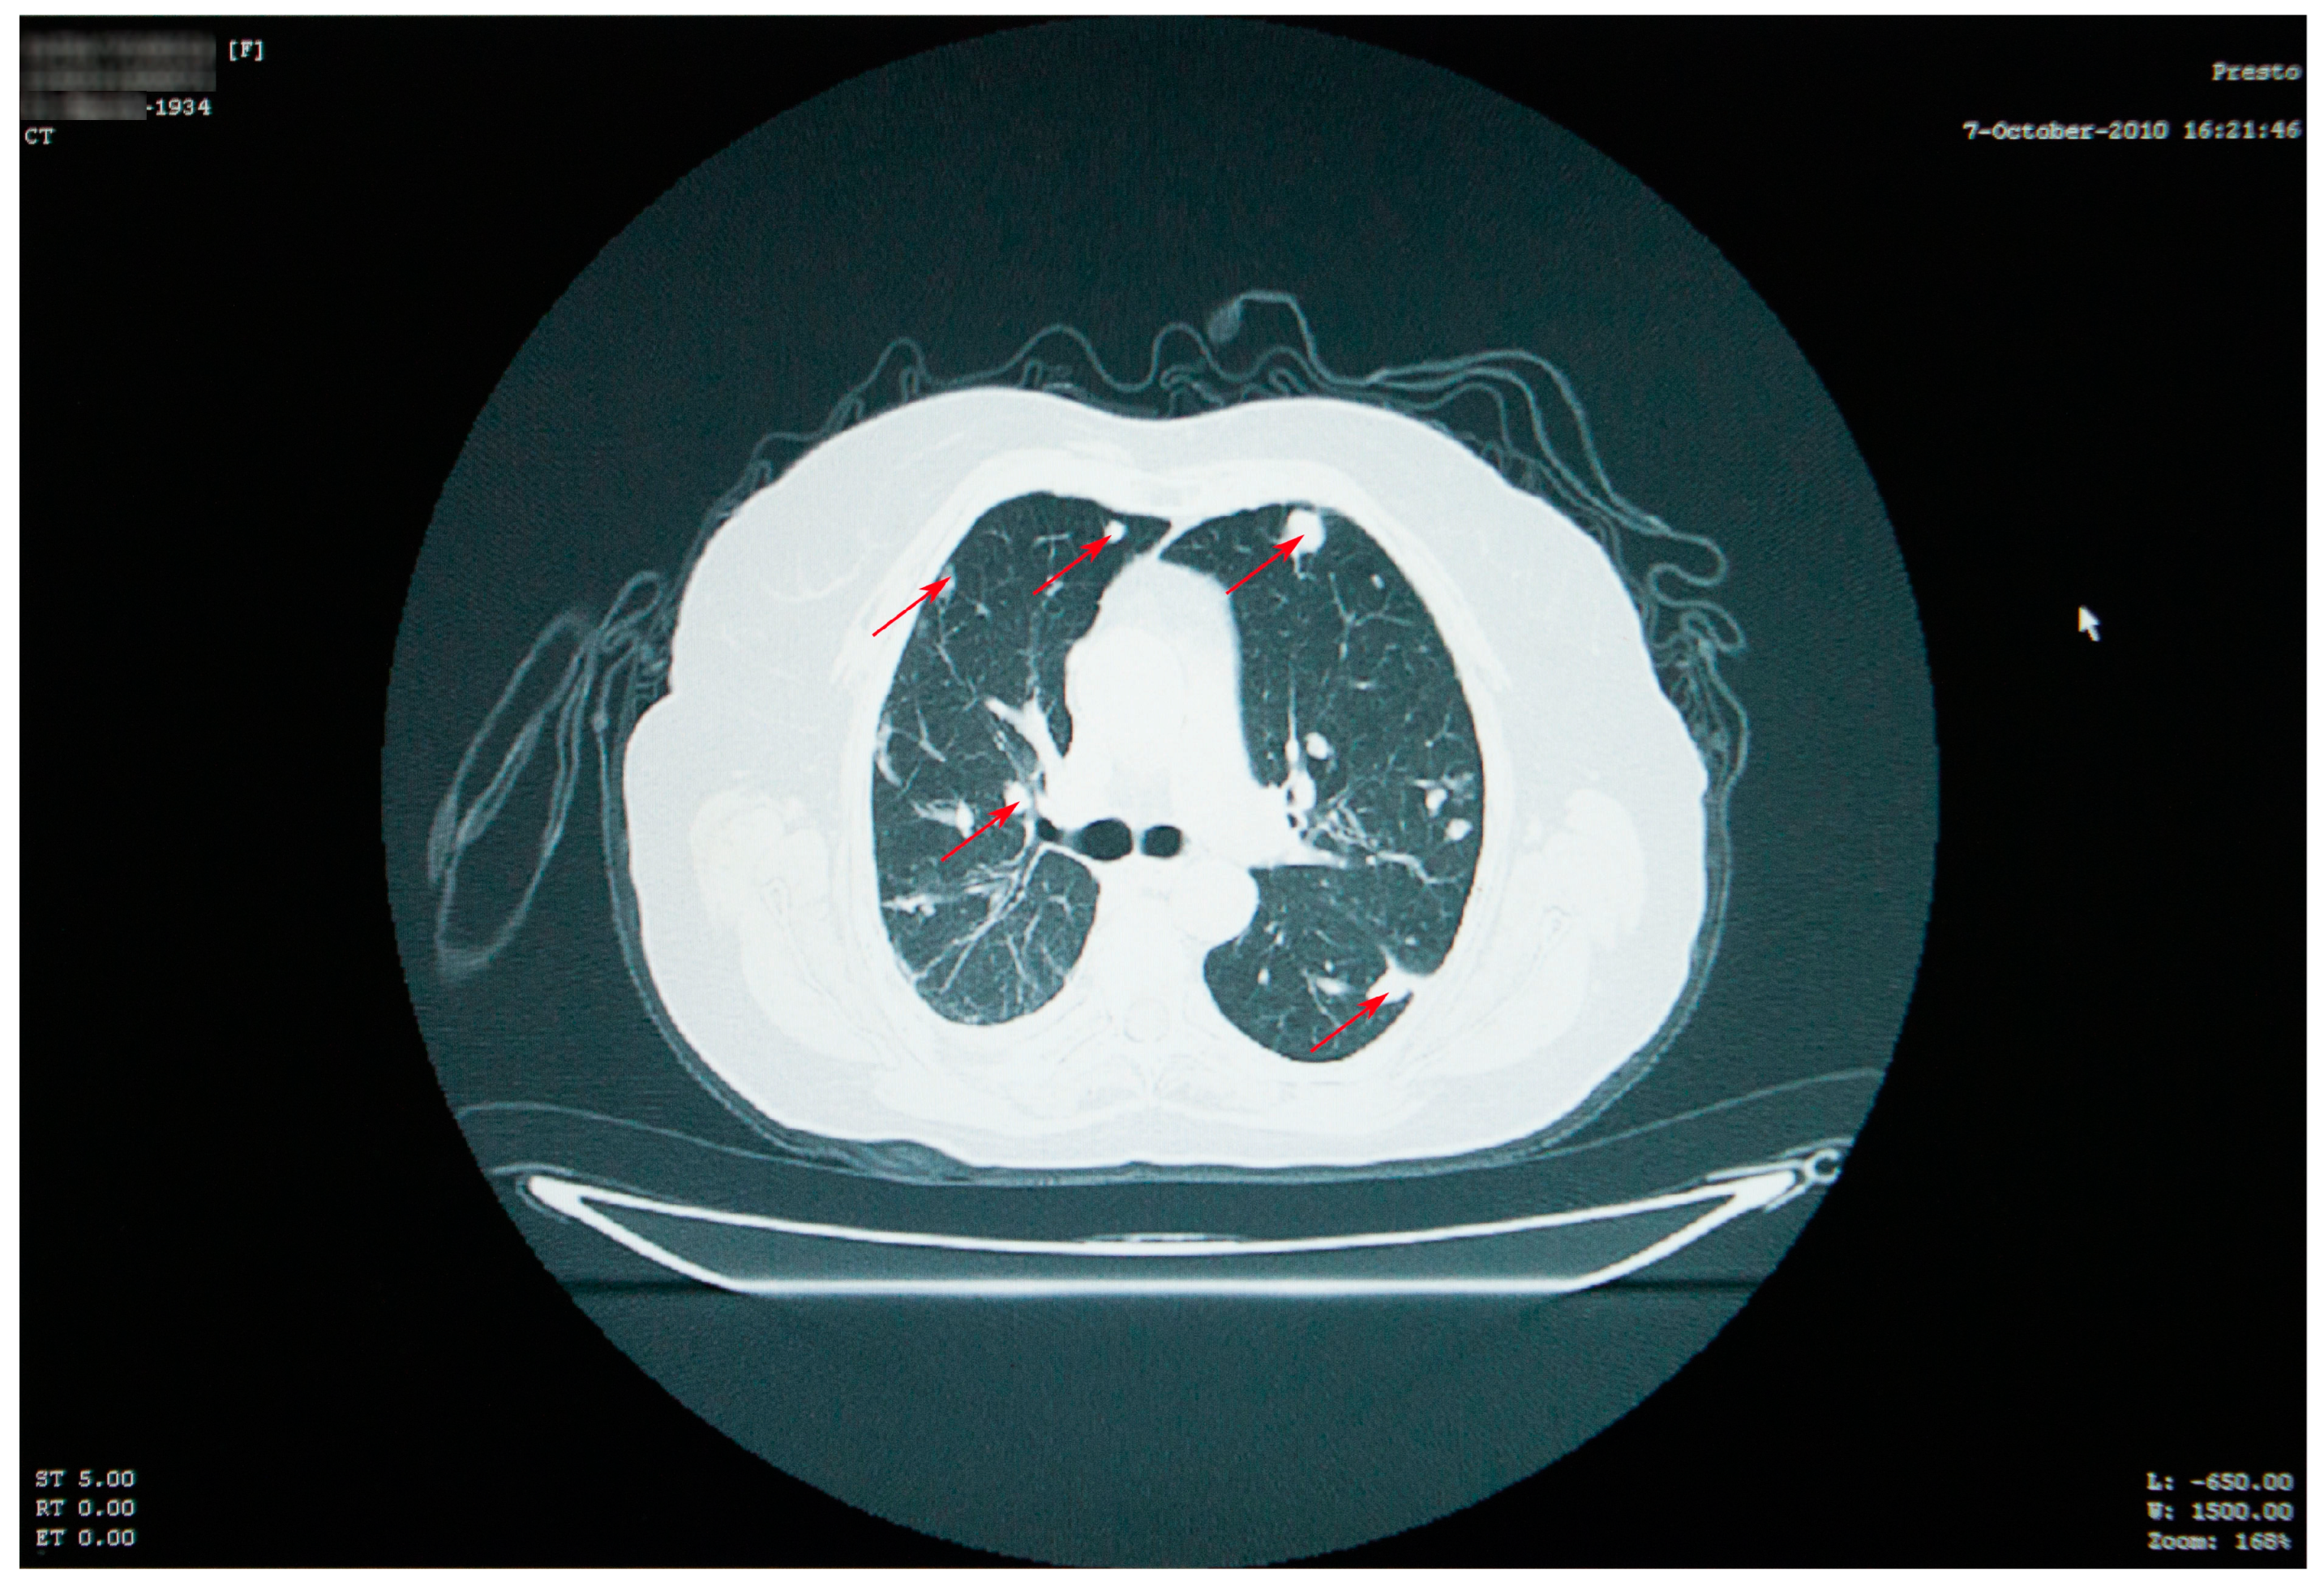

A favorable evolution of the cysts under antiparasitic treatment was observed in October 2009 and March 2010 (Figure 4).

Multiple solid lung masses were described, some with a nodular appearance, some spiculated extensions, some with well-defined borders, and in the approximately same position as the nodular masses from 2006, although obviously diminished in size and with a global change in terms of appearance and contour (Figure 5). The number of masses was unchanged since the previous CT scan; the posterior and right lateral thoracic fibrotic pleural alterations remained; the right pachy-pleuritis was more visible in the right posterior and superior areas.

Figure 5. Thoracic CT showing a reduction in the appearance and dimensions of the cysts (red arrows), which is associated with favorable evolution under treatment.